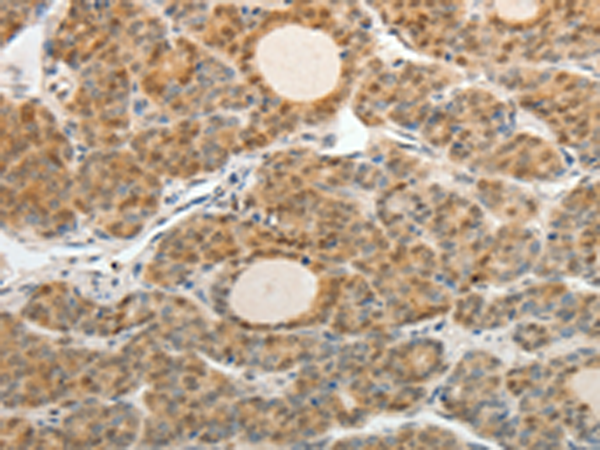

分类: 科研抗体货号: P10723别名: KGF; HBGF-7应用: IHC反应种属: Human, Mouse, Rat